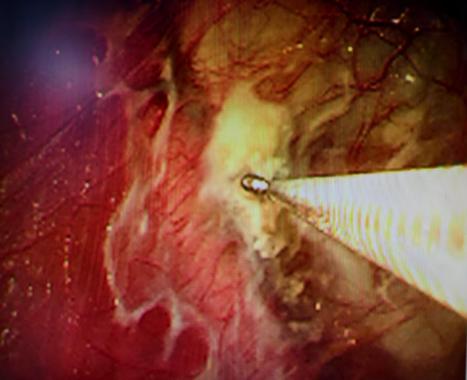

近期,国内知名呼吸介入专家陈愉教授联合我院呼吸与危重症医学科团队,为李先生施行“胸腔镜下肺大疱探查术 + 胸腔闭式引流术”。手术中,陈愉教授运用单孔胸腔镜技术,仅在患者胸壁开了一个1cm的小切口。通过高清胸腔镜系统探查发现,患者胸腔内存在广泛粘连以及多发微小肺大疱,肺叶解剖结构异常,肺门血管直接暴露,经判断肺大疱腔已与胸腔贯通。

面对这一复杂状况,陈教授凭借丰富的经验果断调整手术方案。在确保安全的前提下,对可疑病灶进行了精准活检取样,随后精准置入胸腔引流管。术后即刻CT确认引流管位置良好,同时制定了严密的术后管理方案:每日监测引流量及肺复张情况,若引流量持续减少且肺大疱逐渐缩小,则按计划拨管;若肺大疱未明显缩小,则考虑拔除引流管后转外科进行胸膜剥离术。

“这种微创手术具有创伤小、疼痛轻、恢复快等优点。”陈愉教授介绍,“对于肺大疱患者,早期干预能够避免自发性气胸等严重并发症的出现。不过,手术方案需要根据术中探查结果灵活调整。对于复杂肺大疱病例,精准的术中判断和个体化的术后管理同样关键。活检有助于明确病变性质,而严密的术后监测能保障治疗效果,必要时可及时调整治疗方案。”

(胸腔镜下可见胸腔粘连、多个微小肺大疱)